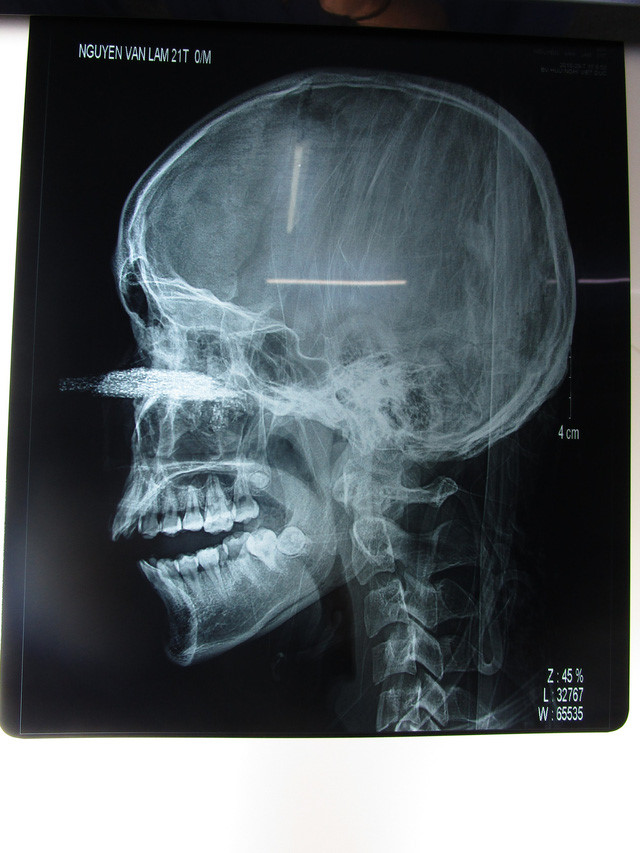

Hình ảnh chụp X-quang cho thấy lưỡi cưa đâm sâu vào bên trong. Ảnh: Dân Trí |

Các bác sỹ khoa Hàm mặt – Tạo hình – Thẩm mỹ đã hội chẩn cùng các bác sĩ chuyên khoa mắt đã tiến hành phẫu thuật nhiều giờ đồng hồ để loại bỏ lữa cưa có kích thước dài khoảng 12 cm cắm sâu vào xoang hàm trên cùng nhiều dị vật nhỏ khác.